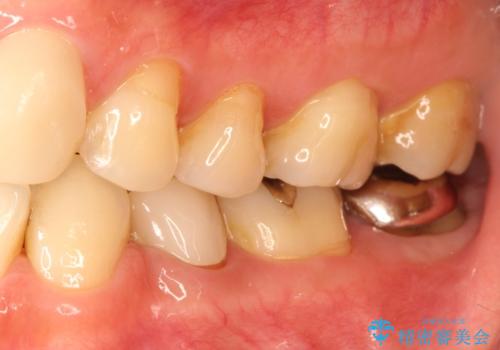

奥歯が痛い。根管治療からセラミッククラウン

咬合力が強くかかる部分には欠けるリスクのほとんどない金属を用いることが最良ですが審美性に劣ります。

今回は白い材料での修復を希望されたため、セラミッククラウンにて治療を行いました。